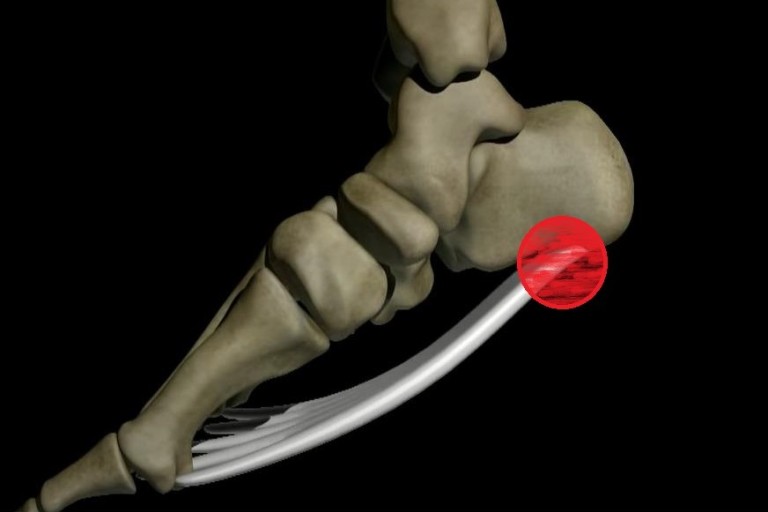

족저 근막염은 발바닥에 위치한 족저근막에 염증이 생기는 질환으로, 발꿈치에 통증을 유발합니다. 주로 하루 중 첫 번째 걸음에서 통증이 심하게 나타나며, 장기간 서 있거나 걷는 것에 어려움을 겪을 수 있습니다. 과도한 운동이나 비만, 잘못된 신발 착용 등으로 발병할 수 있습니다.

족저 근막염의 가장 흔한 증상은 발꿈치 통증입니다. 첫 걸음을 디딜 때 통증이 가장 심하며, 일상적인 활동 중에도 통증이 발생할 수 있습니다. 통증은 발꿈치 안쪽에서 느껴지는 경우가 많습니다.

족저 근막염의 치료에서 중요한 것은 발바닥과 종아리 근육 스트레칭입니다. 발꿈치 근육을 풀어주는 스트레칭을 꾸준히 하면 통증 완화에 도움이 됩니다.